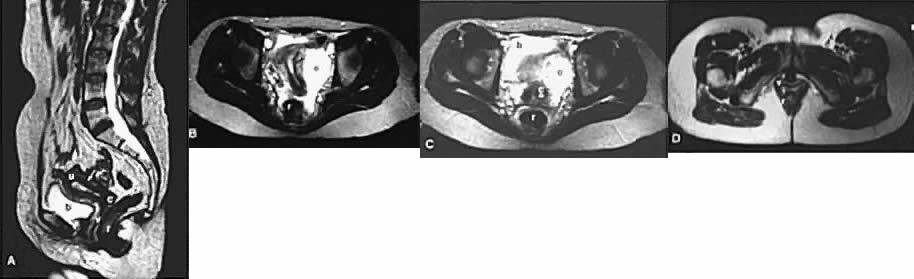

With its improved soft-tissue contrast resolution and multiplanar capability, MRI is very useful in local staging of cervical carcinoma. Low signal intensity surrounding the tumor in the cervix and preservation of fat planes are consistent with tumor confined to the cervix (Fig. 14A). Stage IIA is indicated by the loss of the normal low signal intensity of the vaginal wall (Fig. 15). Stage IIB is indicated by the presence of abnormal thickening of the parametrium on T1-weighted MRI (see Fig. 2A; Fig. 16A). On T2-weighted images, stage IIB is depicted as increased signal intensity in the parametrium with the loss of the normal low signal intensity of the cervical stroma.9 Stage IIIA is indicated by the loss of low signal intensity of the wall of the lower third of the vagina. In stage IIIB, the lateral pelvic wall muscles lose their normal low signal intensity, with loss of the fat planes separating these muscles from the tumor on T1-weighted images (Fig. 17A and B). Stage IVA is indicated by loss of the normal low signal intensity of the bladder wall (see Fig. 17D; Fig. 18) or rectal wall (Fig. 19), associated with wall thickening and/or intraluminal mass.26,27

Fig. 17. Recurrent cervical carcinoma with possible radiation changes in the bones and muscles. Sagittal ( A ), low-transverse ( B ), coronal ( C ), and high-transverse ( D) T1-weighted MRI of the pelvis show a large high-signal-intensity mass ( m) (density less than that of fat and more than that of muscle) superior and posterior to the bladder ( b ). Note thickening of the right lateral and superior bladder wall caused by tumor invasion ( arrows ). There is also spread of tumor to the pelvic sidewall ( arrowheads ). There is thickening and increased signal intensity to the right iliopsoas muscle ( ip) compared to the left. There is also evidence of increased signal intensity to the bone marrow of the sacrum and L5 in A. The muscle and bone changes are probably caused by radiation.